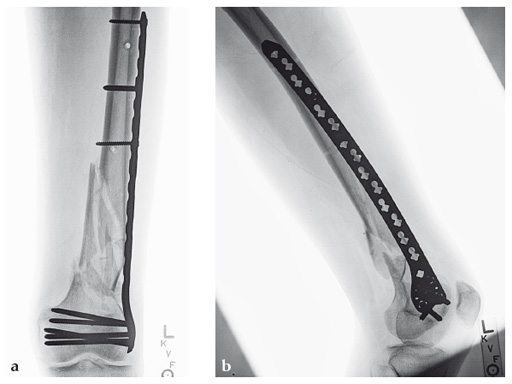

Case 1: A 30-year-old man was involved in a motor vehicle collision and sustained an isolated extraarticular multifragmentary supracondylar femoral fracture (33-A3).